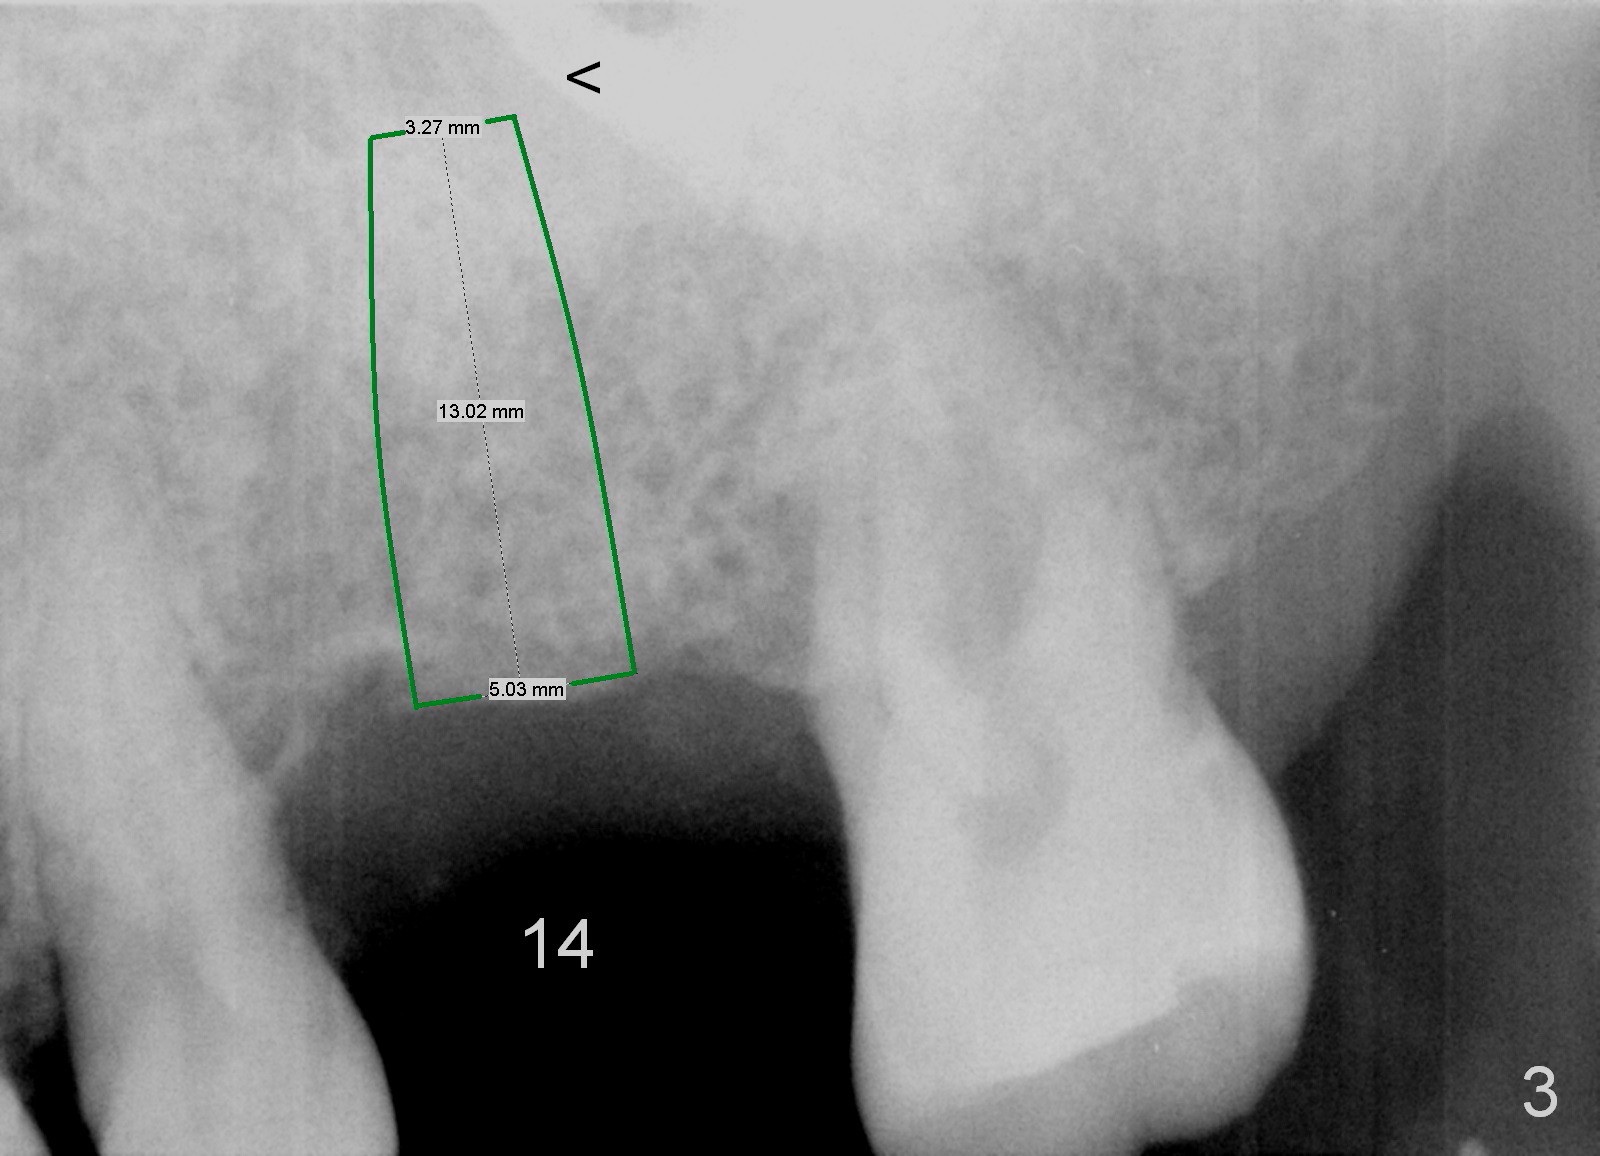

Implant placement at #31 reveals that bone width (bucco-lingual) is not a problem for a 64-year-old man. He requests implant placement at #7 and 14 (Fig.1,3), because the upper flipper has been lost. He wants to make sure that the implant at #7 does not cause the pain at #6. In fact the flipper appears to have lead to caries (Fig.2 *) and periapical radiolucency (<) at #6. RCT is rendered at #6 prior to a 1-piece implant at #7 (Fig.1). Since bone height is sufficient, the implants do not have to penetrate the nasal floor (Fig.1 v) or the sinus floor (Fig.3 <) unless the bone density is low. Prepare implant positioner of 4 mm to determine whether the ridge is wide to hold a 3.8 or 4 mm implant. Take preop photos to show the ridge width.

Re-analysis of #14 edentulous area reveals slightly unfavorable crown/implant ratio if the implant reaches the 1st line of the sinus floor (Fig.4). A 5x13 mm implant may invade the 1st line (Fig.5). Therefore the depth of osteotomy using 4.8 mm Magic Drill is 9-10 mm (Fig.6 green), followed by Magic Sinus Lifter, unless the bone density is high.